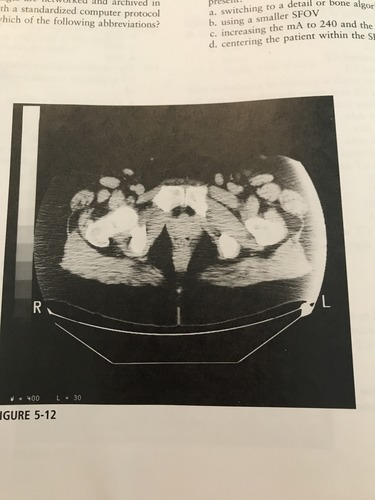

The artifact present on the lateral borders of the image in the figure most likely represent which of the following?

A) edge gradient

B) out of field artifact

C) tube arcing

D) beam hardening

B) out of field artifiact

The image in the figure was produced using: large (FULL) SFOV; max DFOV (48cm); 200mA; 120 kVp; soft tissue algorithm. Which technical adjustment would serve to reduce the artifact present?

A) switching to a detail or bone algorithm

B) using a smaller SFOV

C) increasing the mA to 240 and the kVp to 140

D) centering the patient within the SFOV